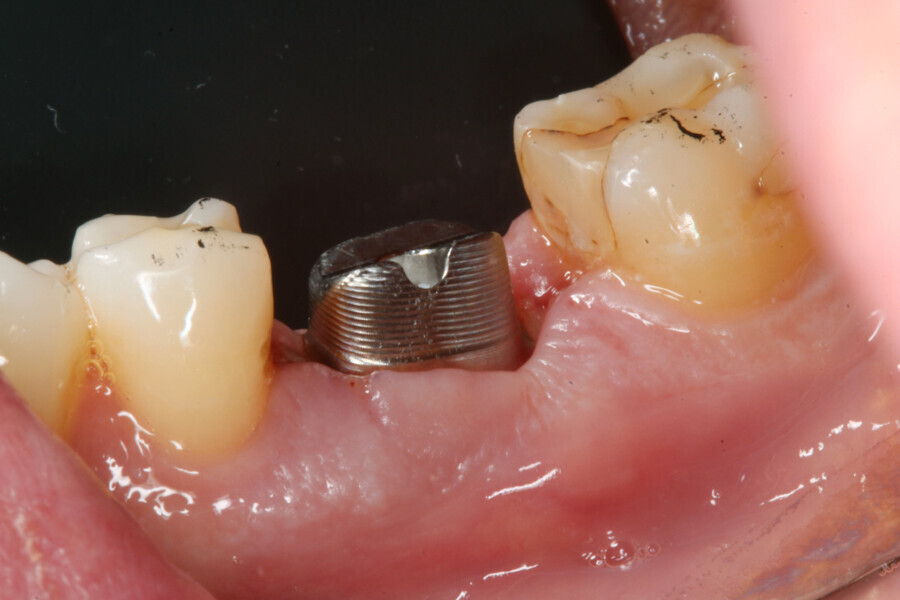

A 39-year-old male patient presented with a deeply fractured mandibular first molar two years after hemisection (Fig. 1). After the patient had opted for an implant-borne solution, an immediate implant placement and restoration with a PMMA provisional crown on a final Atlantis abutment (Dentsply Sirona) was planned.

The implant site was prepared following the recommended drilling protocol for the planned PrimeTaper EV 4.2 mm diameter implant (drills #1, 3 and 4; Fig. 2). After cortical preparation with drill #5, the implant was placed. The preparation was finalised with a tap, owing to dense trabecular bone (Fig. 3). The implant was inserted to a torque of 42 Ncm (Fig. 4).